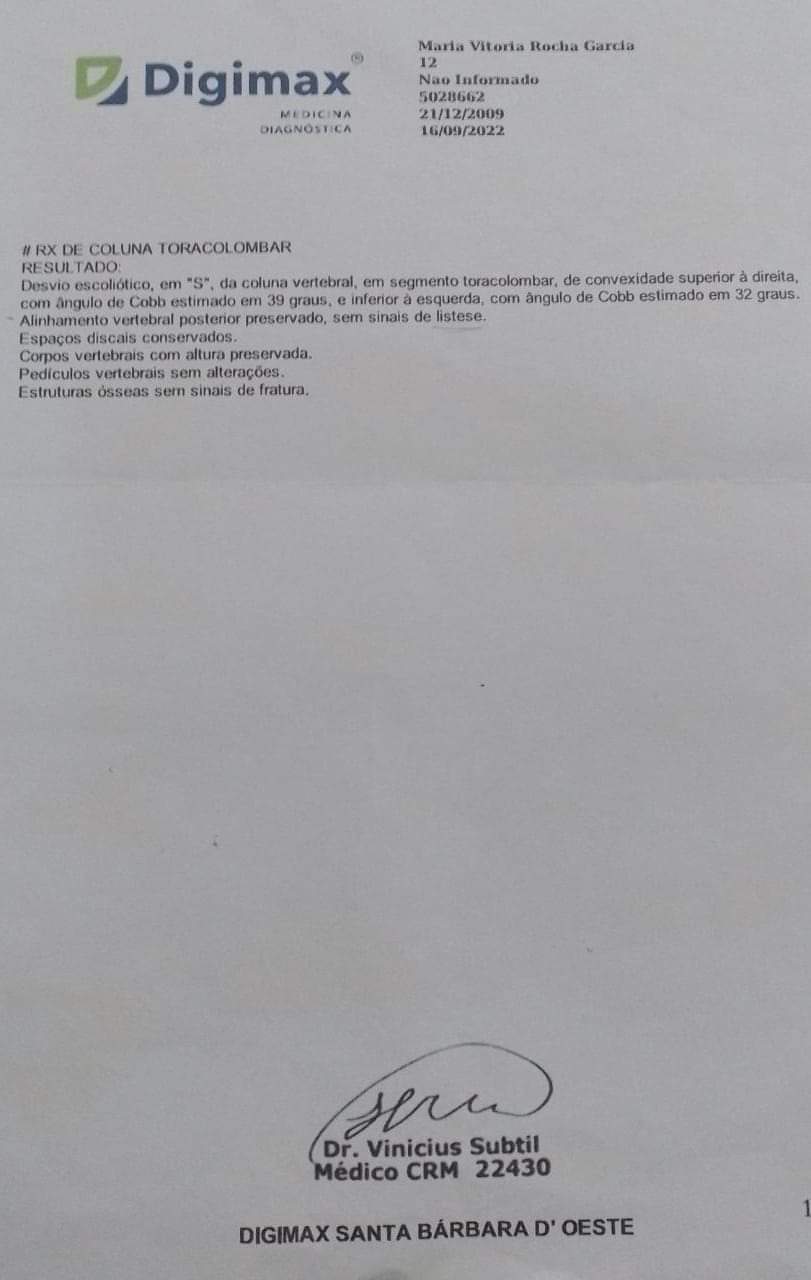

Há um ano mais ou menos descobrimos que tenho escoliose na coluna com uma curvatura mais de 39 graus. Já fiz muitas sessões de fisioterapia recomendada pelo médico, mas de nada adiantou. Minha mãe já fez tudo ao alcance dela, passei no núcleo com a ortopedista Jenifer. Ela me encaminhou para a regional porque está avançado meu caso, e pode prejudicar os meus órgãos, principalmente o pulmão, tenho muita dor, não consigo dormir, os medicamentos que tomo para dor não resolvem e podem me prejudicar futuramente..